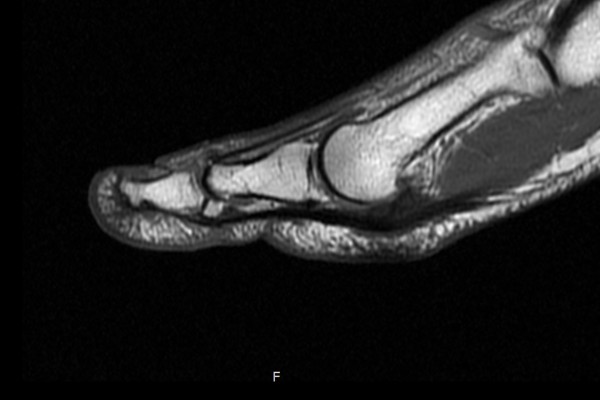

MRI 촬영결과 발가락을 들어올리는 힘줄인 장무지신전건(힘줄) 부착부 파열

(Lt. foot 1st toe Extensor Hallucis Longus (EHL) avulsion tear)이 확인되었습니다.

아래에 힘줄을 보면 검은색 힘줄이 잘 연결되어있으나 위에 장무지신전건을 보시면 파란 점선처럼

연결되어있어야 할 힘줄이 끊어져있는것이 확인됩니다.